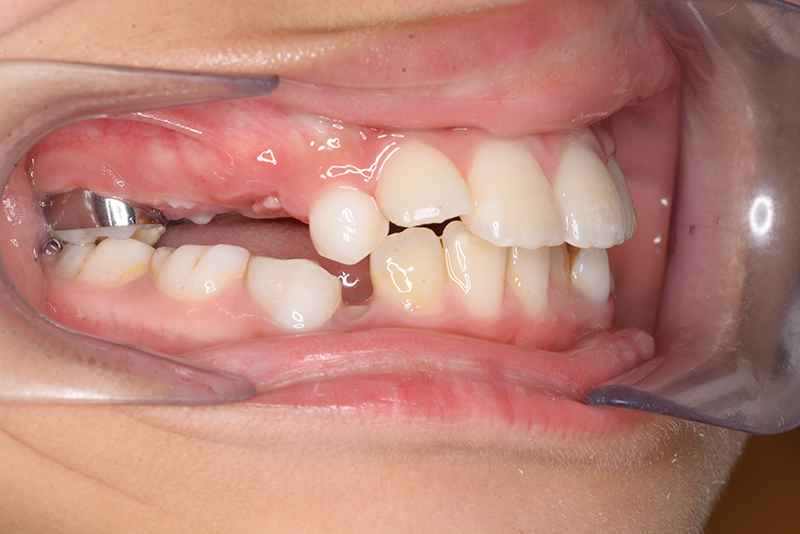

| 口腔内所見 | over jet 2.5mm、over bite 2.0mm、右側大臼歯関係はEnd on class Ⅱ、上顎左側Eは早期喪失により左側大臼歯関係はFull classⅡ、右側Eは6の異所萌出により歯根吸収が進行したため一般歯科医院にて抜去済みであった。 |

| パノラマ所見 | 上顎両側6、特に左側6は近心傾斜が認められ、両側5の萌出スペース不足が認められた。 |